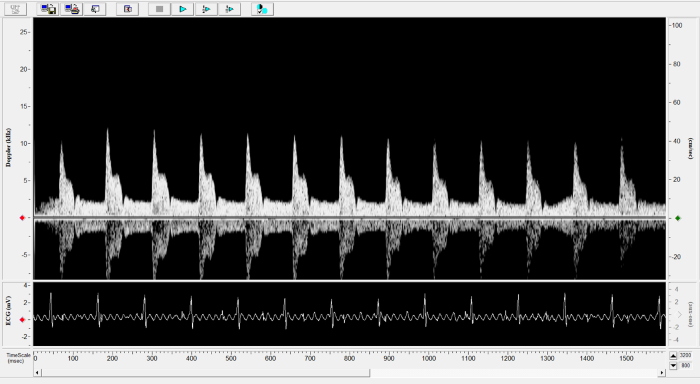

Mouse - Abdominal Aorta

Mouse - Abdominal Aorta. Image Credit: Scintica Instrumentation Inc.